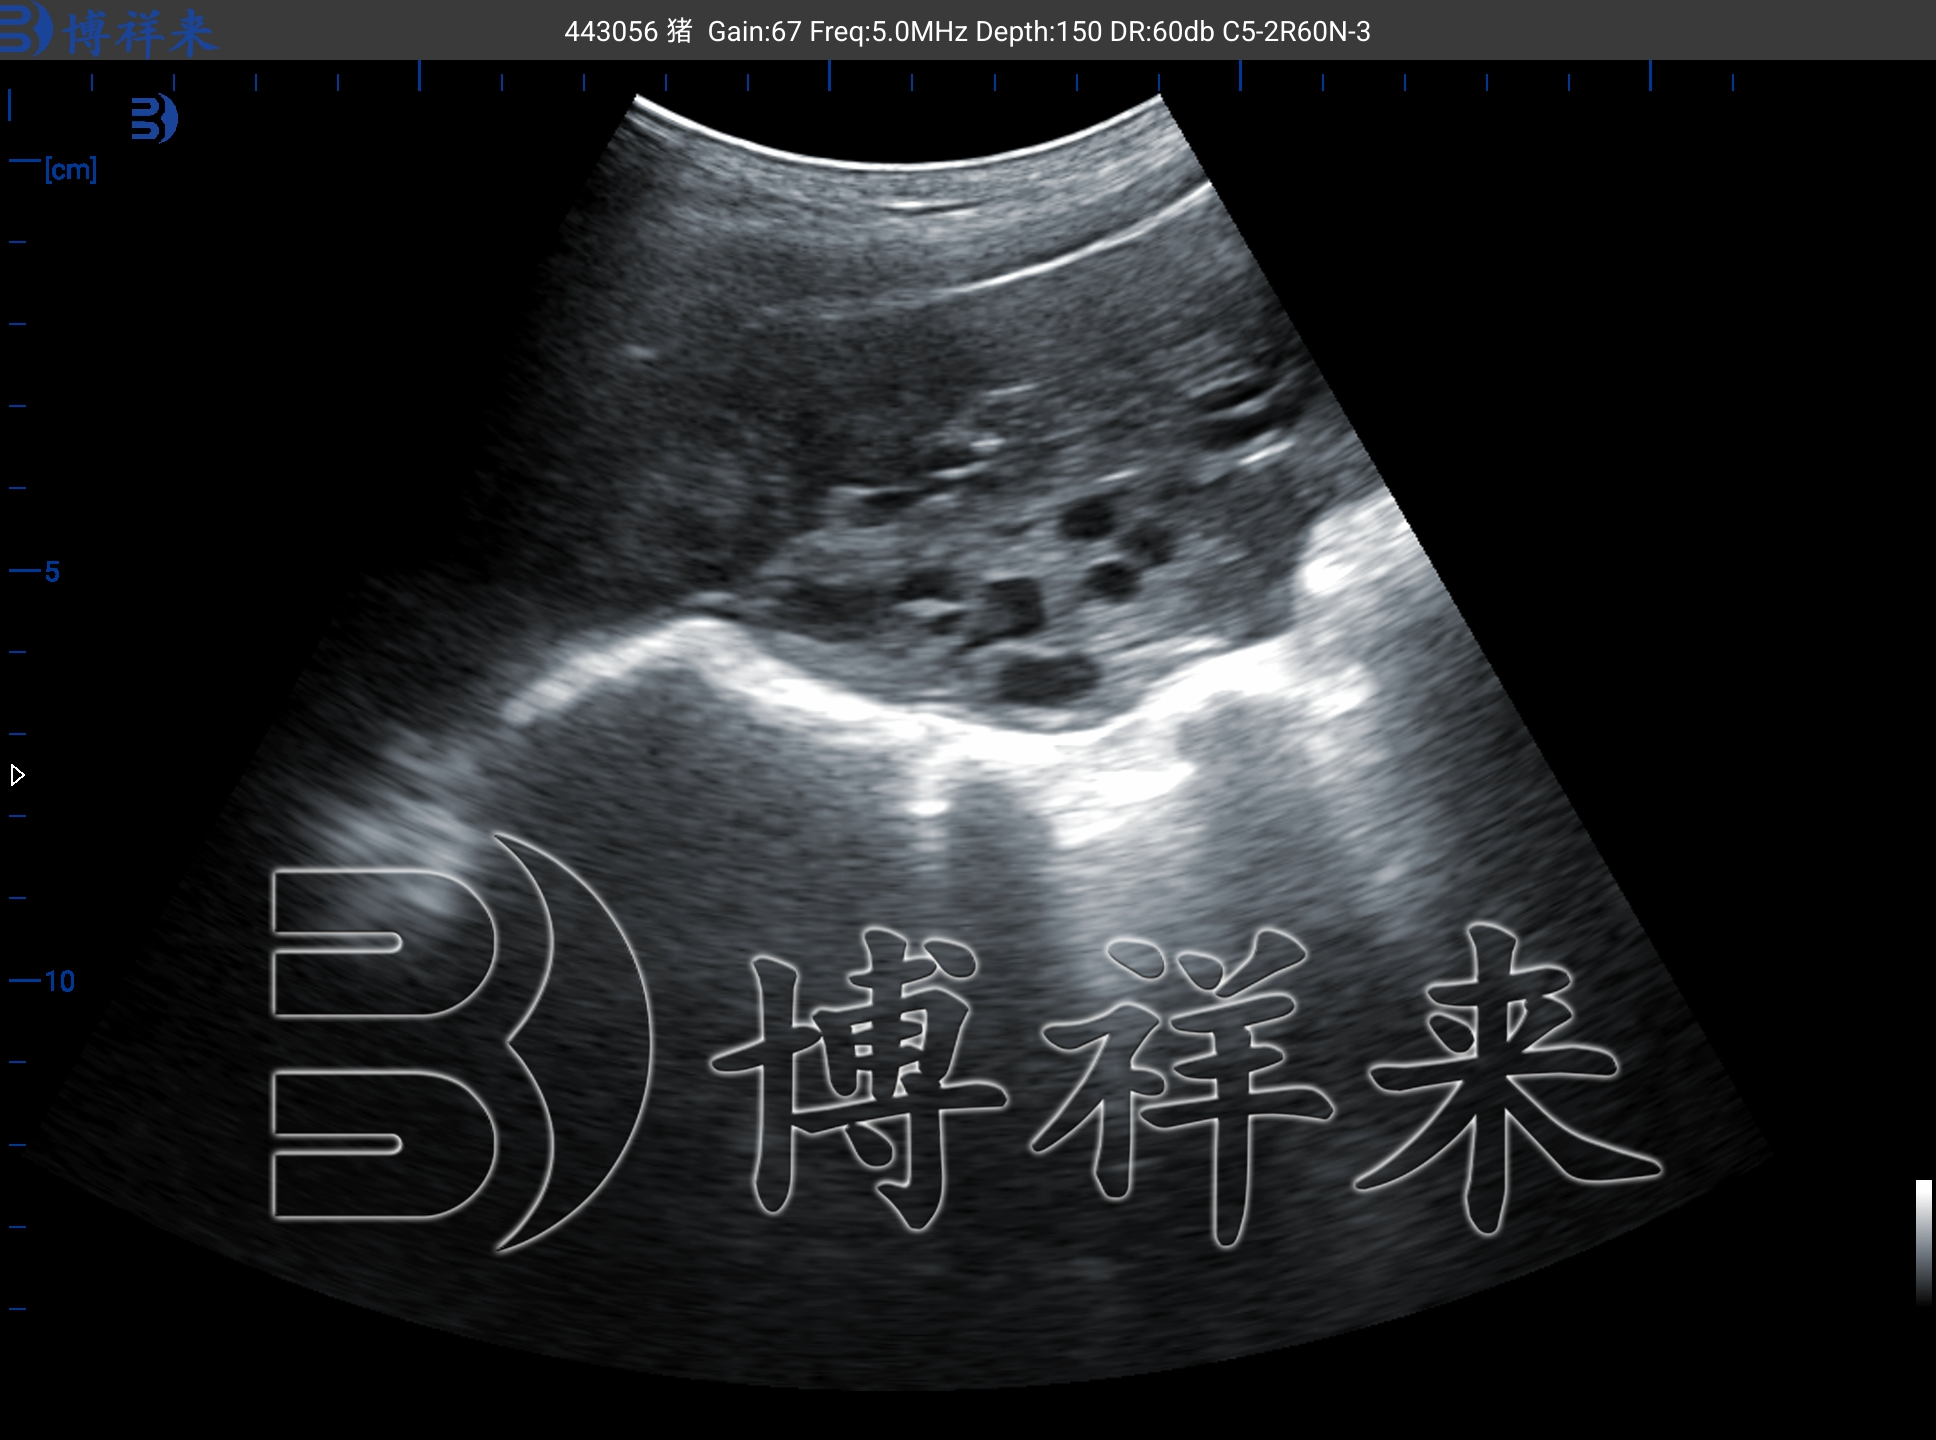

解猪用活体采卵仪在现代规模化猪场中的核心作用。博祥来猪采卵B超机通过非手术方式,助力高价值种猪基因快速复制,加速遗传改良进程。